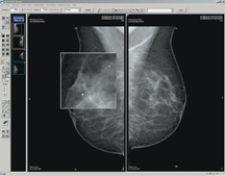

eRAD has received FDA 510(k) clearance for soft-copy viewing of digital mammography images. This clearance allows eRAD to market its eRAD PACS Diagnostic Workstation software and FDA-cleared display hardware to the mammography community. In conjunction with this clearance, eRAD is adding several features to its viewing capabilities, including mammography-specific hanging protocols, mirrored rendering tools including panning and magic glass zooming, support for R2 Technology’s ImageChecker CAD markers and BI-RAD support in reports. The product enhancements provide efficient image review, distribution and storage for full-field digital mammography (FFDM) systems.